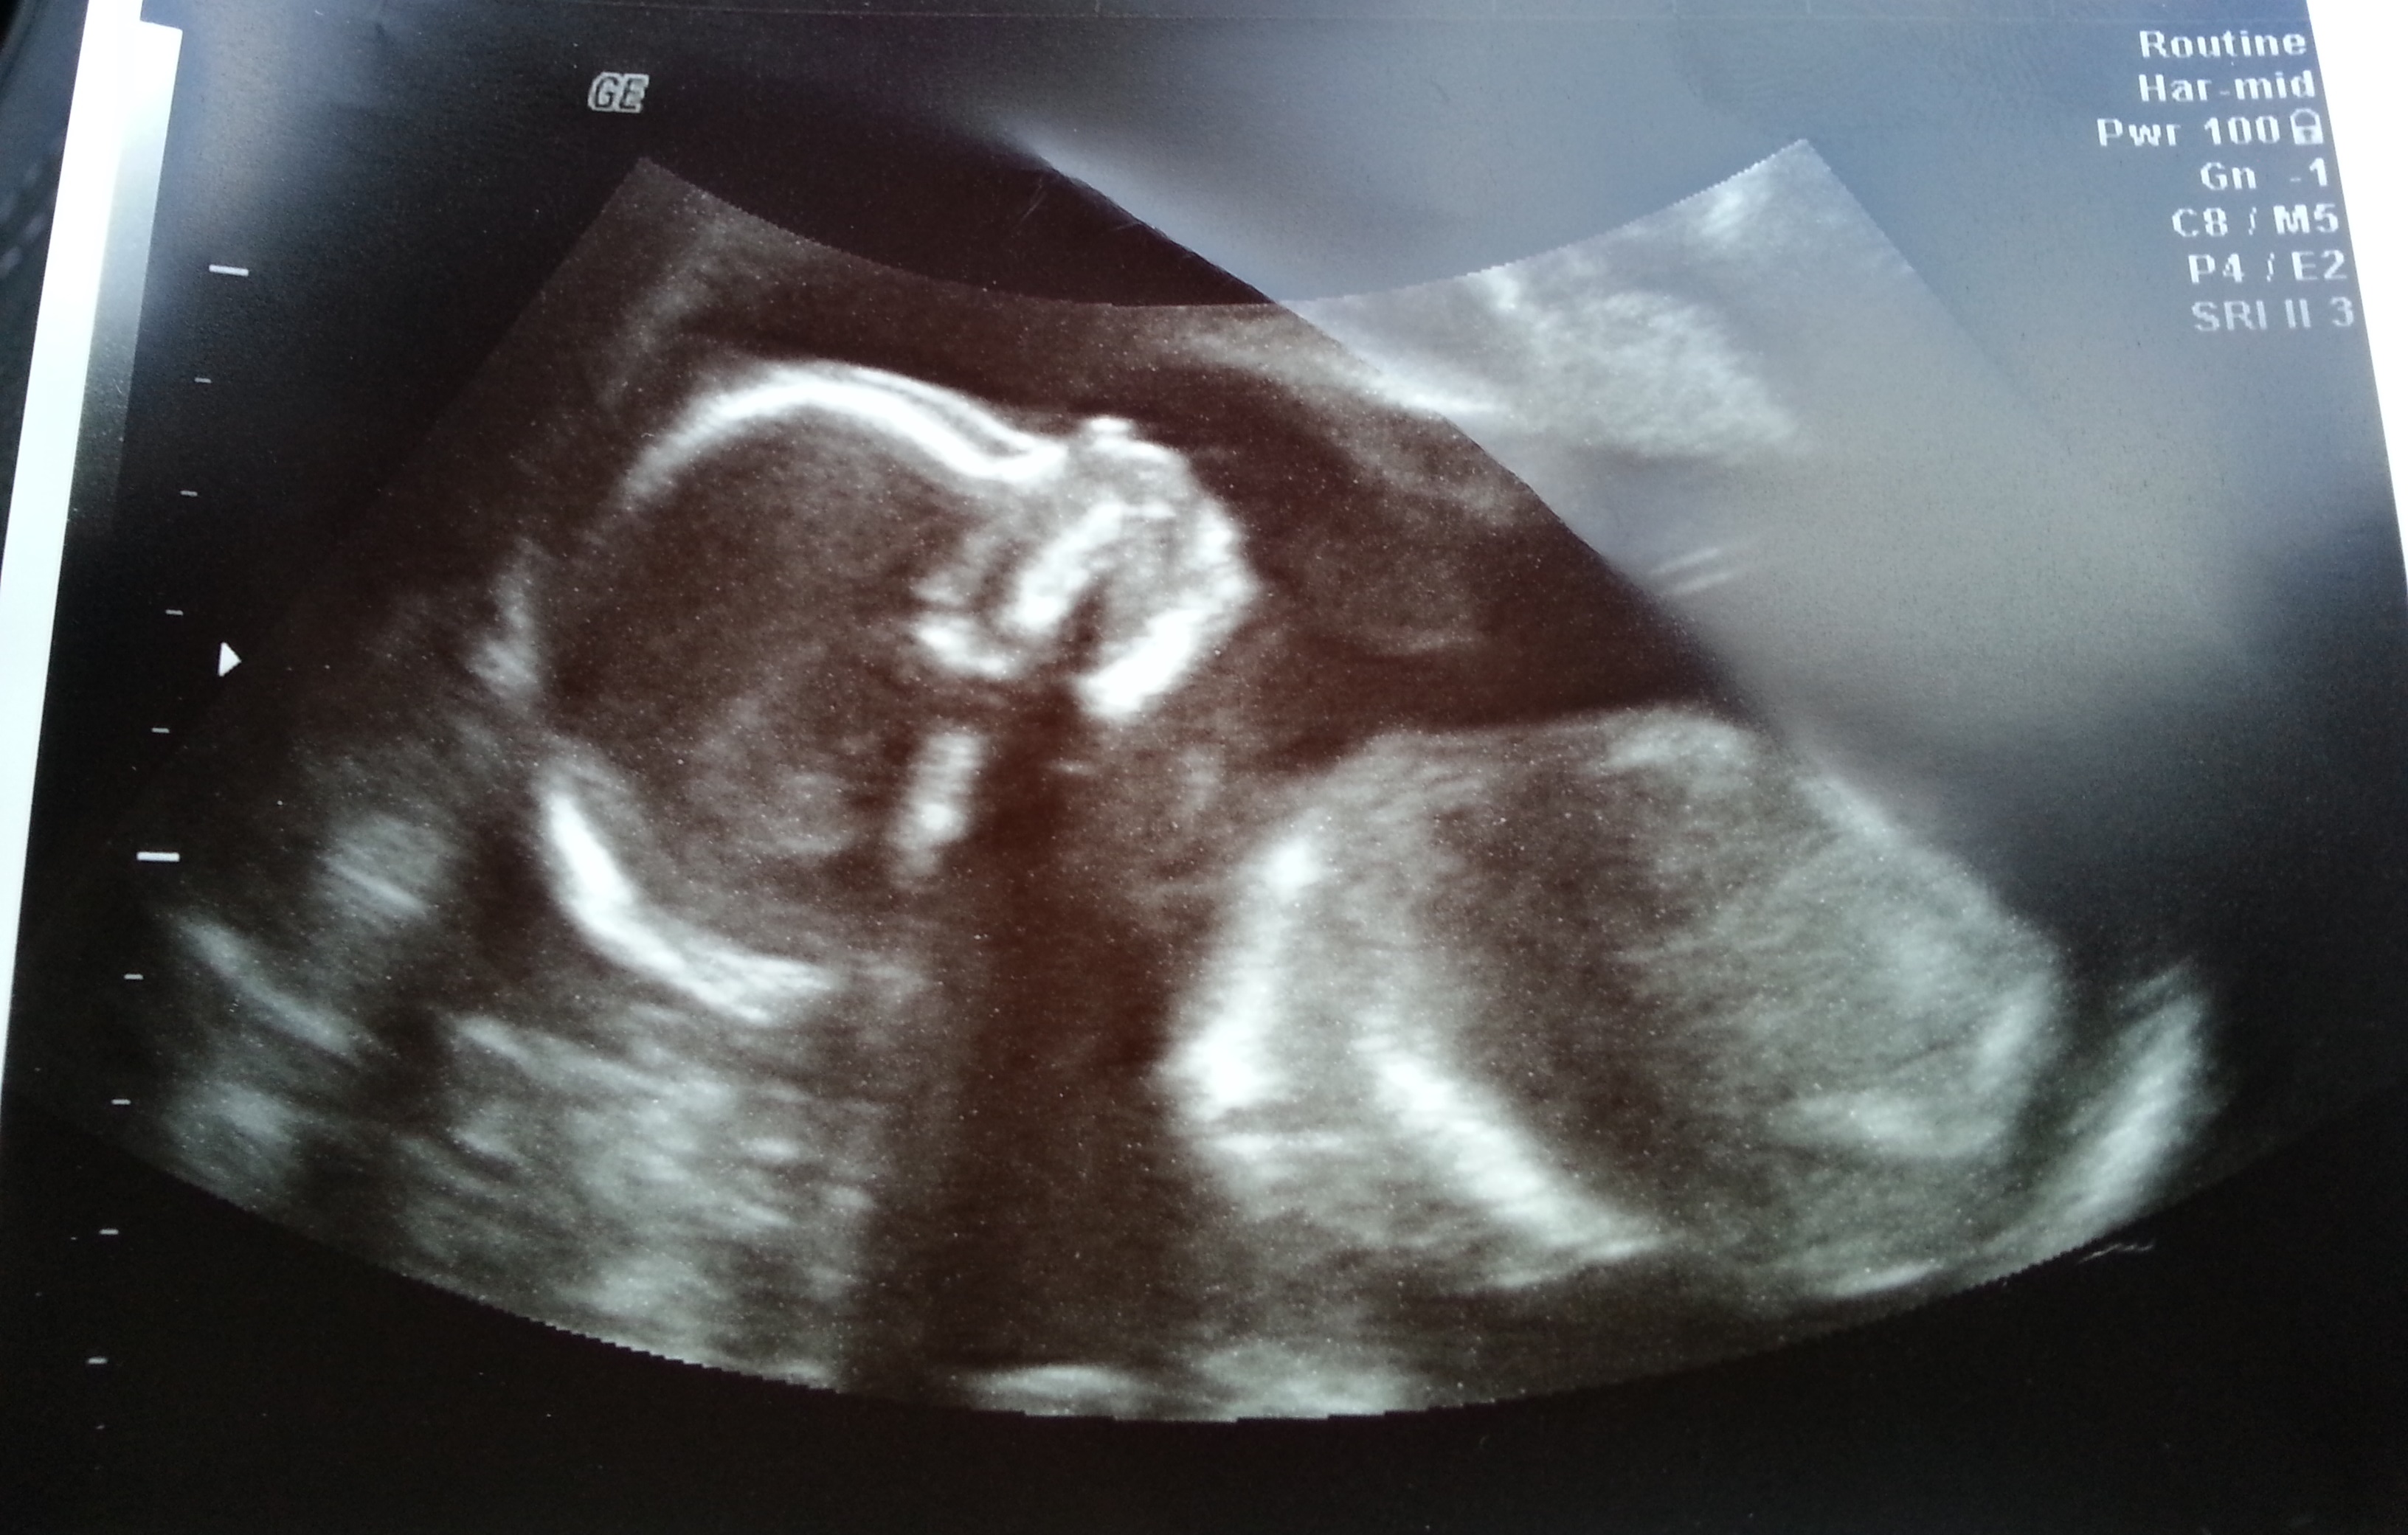

YAY...I finally get to post my A/S.  We were strong and stayed Team Green even though I caught DH every once in awhile trying to cheat but he had no clue what he was looking at haha.  Baby looks great, happy & healthy.  I totally forgot to ask what the HB was but does weigh 10 ozs..  Only little thing was that right now LO is breech but we have plenty of time for that to change.  LO was very cooperative so she was able to go pretty fast until she got to the feet lol then there was some poking and proding lol.  It was so great to see the little munchkin again.  I go for one more scan around 35/36 wk area.

I tried to shrink the pics...Hope they aren't too big.